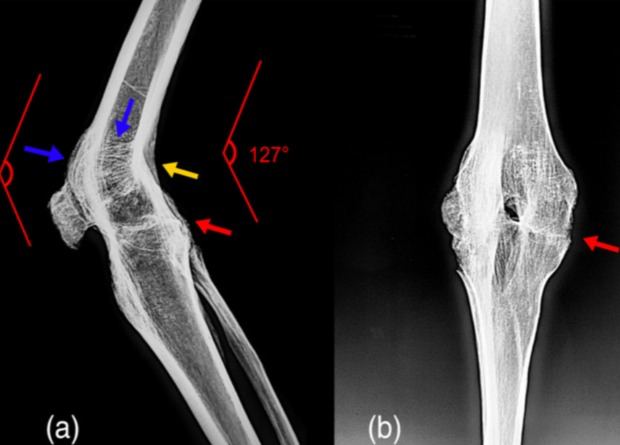

​​Палеопатологи обнаружили у древнего кочевника из Синьцзяна неподвижность коленного сустава — анкилоз. Он умер в возрасте 35–45 лет в VI–IV веках до нашей эры, прожив со своей патологией несколько лет. В этом он оказался похож на отца Александра Македонского — царя Филиппа II, у которого анкилоз развился после ранения копьем в колено